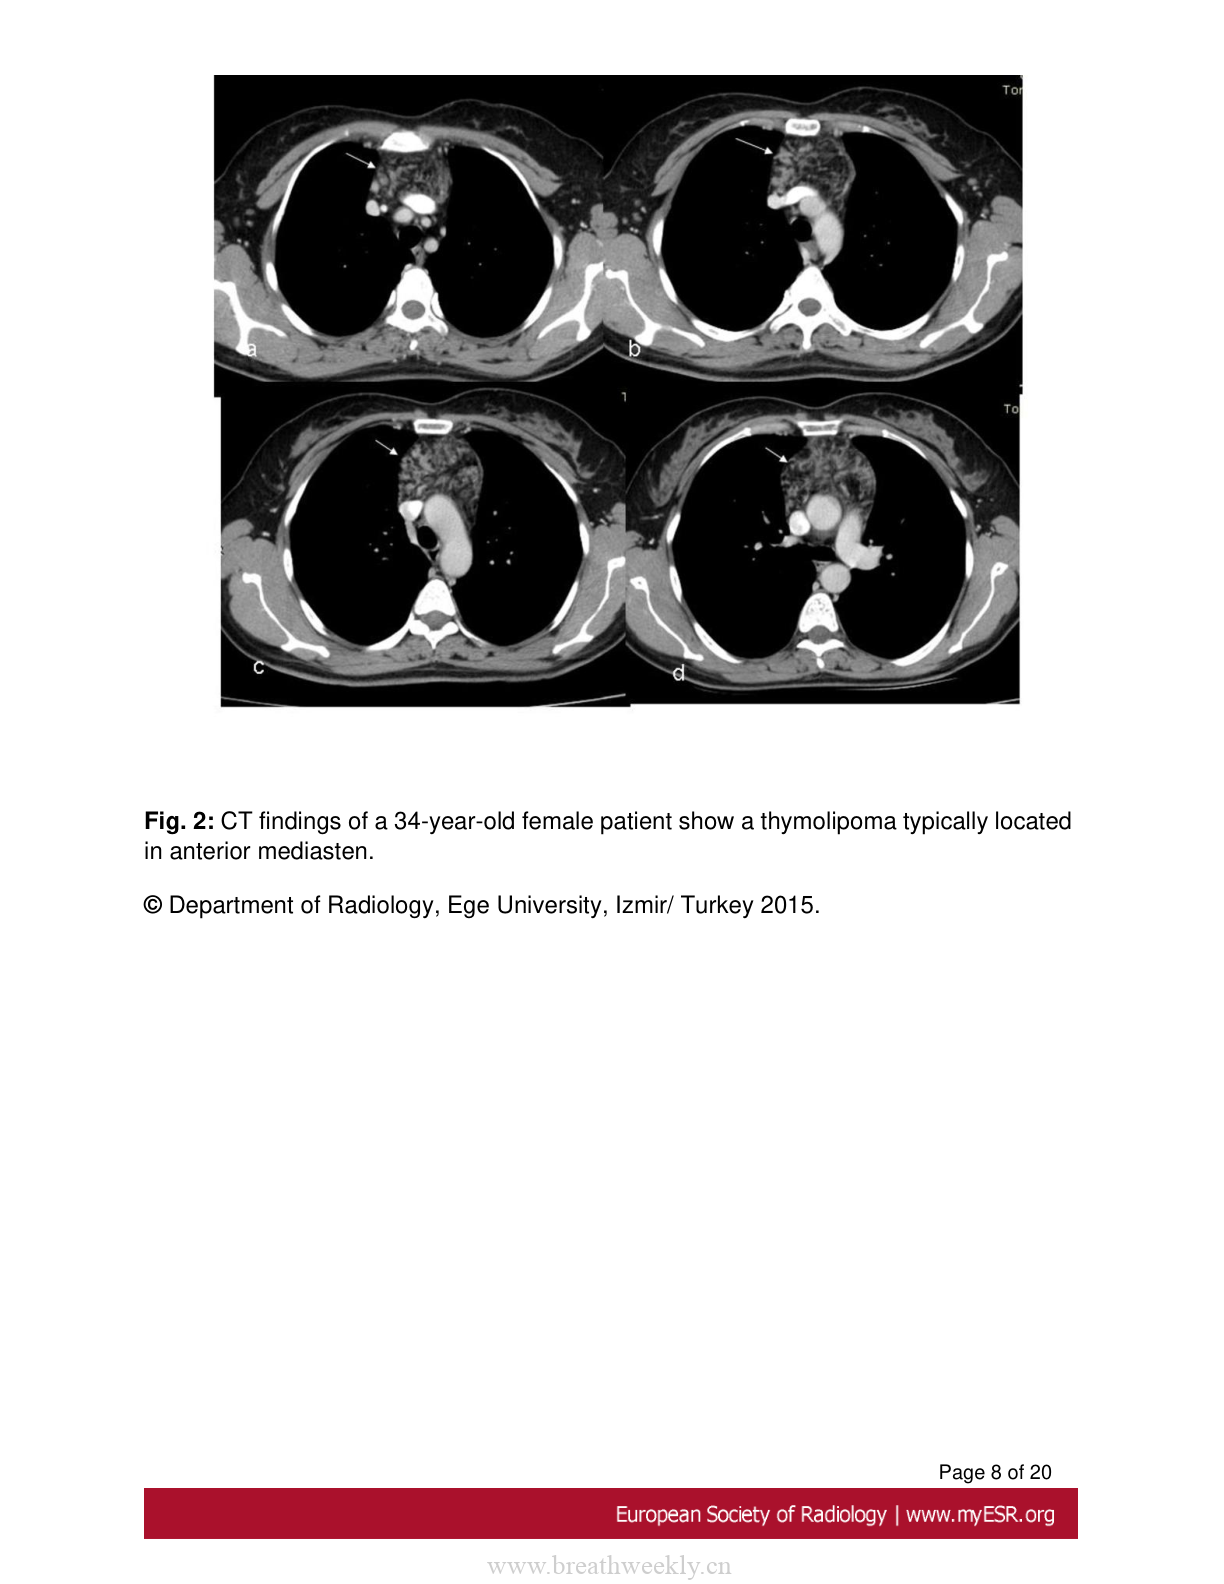

图2:胸腺脂肪瘤典型病例

34岁女性患者的CT表现,显示典型位于前纵隔的胸腺脂肪瘤。